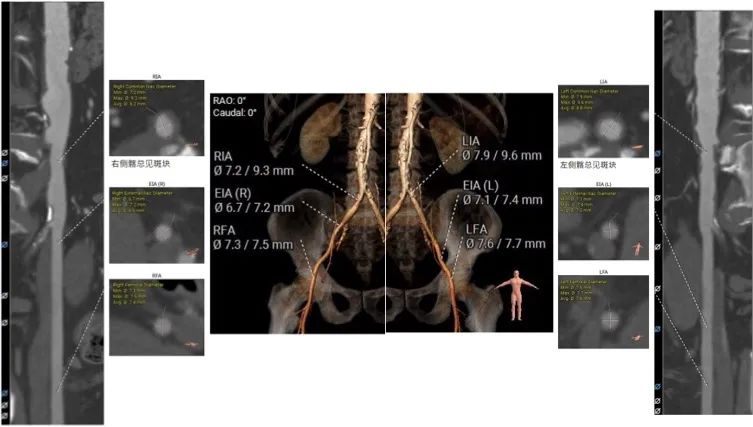

股动脉入路:

主入路:右侧股动脉

辅入路:左侧股动脉